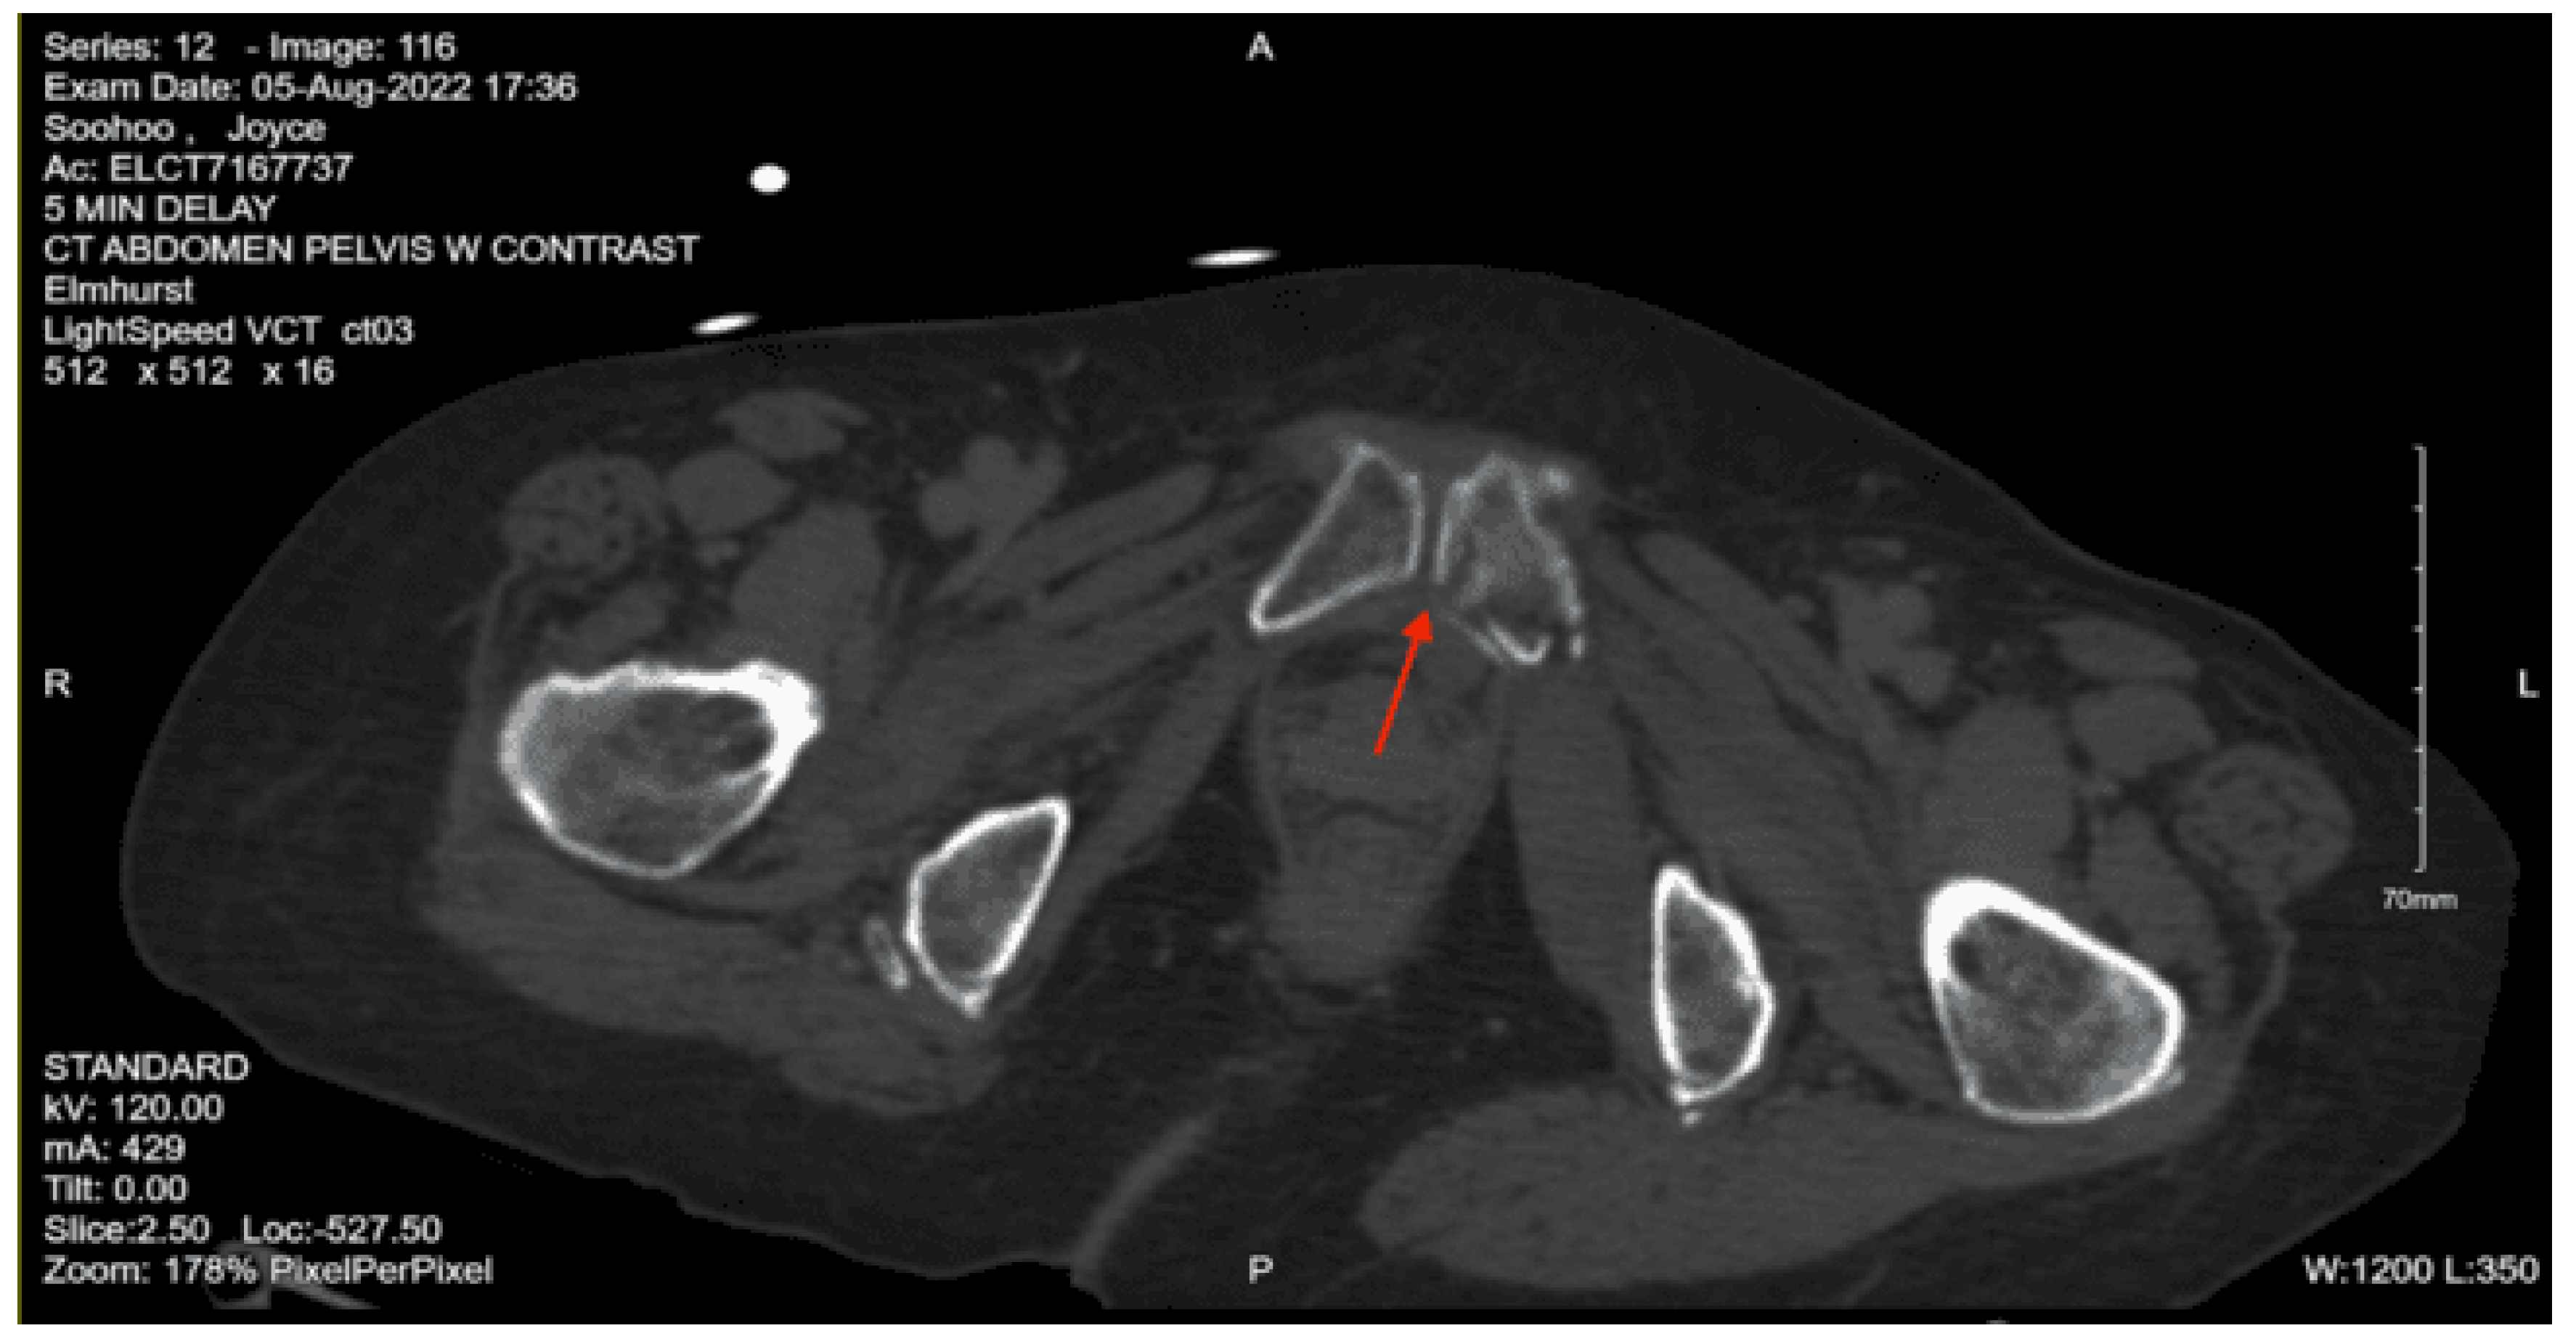

Imaging as shown in Figure 27, Figure 28 and Figure 29:

CT abdomen pelvis with contrast: There is retroperitoneal fluid surrounding the upper abdominal aorta without contrast blush. Linear flap within the upper abdominal aorta at the level of the celiac and SMA origins, concerning for traumatic injury. Lower thoracic findings include multiple posterolateral right rib fractures. Grade II hepatic injury. Periportal edema. Acute right L1 through L5 transverse process fractures. Acute right sacral ala fracture. Nondisplaced acute right inferior pubic ramus fracture. Nondisplaced acute fracture involving the lateral aspect of the right acetabulum.